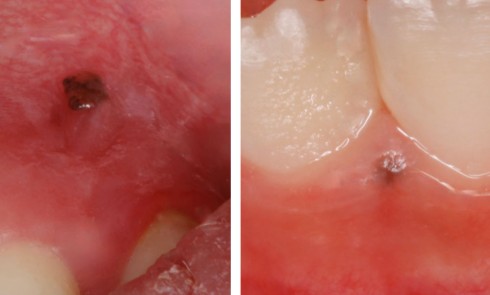

Article réservé à nos abonnés Quand c’est noir, ça inquiète !

CAS 1 Motif de la consultation Patiente de 44 ans venue consulter sur les conseils de son dentiste traitant après la découverte,...